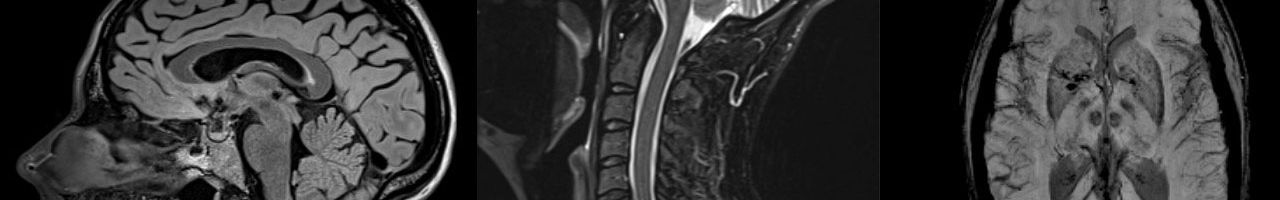

The Research MRI Core provides resources at UAB for state-of-the-art magnetic resonance imaging experiments and analyses for examining brain and body anatomy and function both in health and disease.

Research ranges from basic MRI engineering and physics to multisite clinical trials. We support investigators with advanced imaging of the whole body, including the brain, spinal cord, eye, liver, skeletal muscle, heart, and kidney.